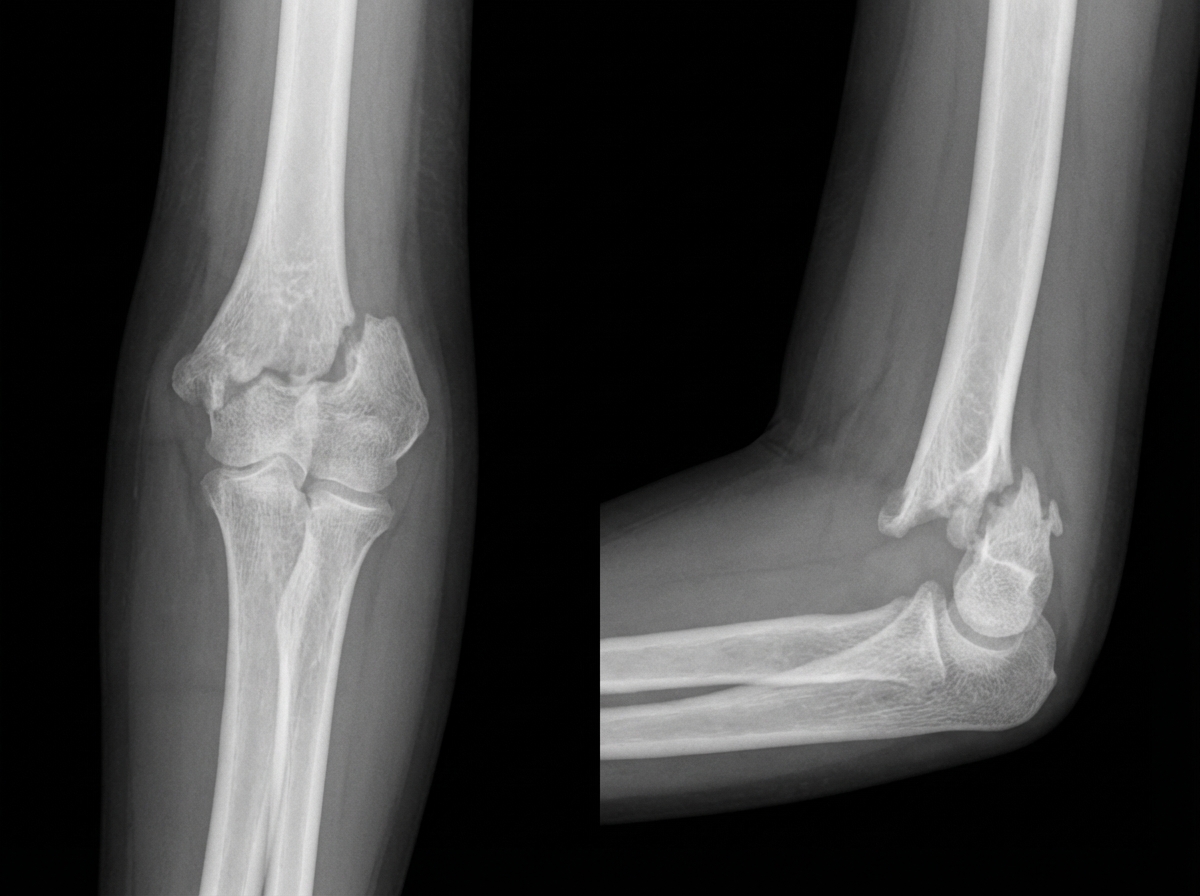

A patient presents with a fall on an outstretched hand. An X-ray is shown below. Which of the following vessels is most likely involved?

Explanation: ***Brachial artery*** - Fall on outstretched hand (FOOSH) typically causes a **supracondylar fracture of the humerus**, where the **brachial artery** runs directly anterior to the elbow joint and is vulnerable to injury from the proximal fracture fragment. - The **brachial artery** is the main vessel crossing the elbow anteriorly, making it the most commonly injured vessel in supracondylar fractures, potentially causing **compartment syndrome** or **Volkmann's ischemic contracture**. *Ulnar artery* - The **ulnar artery** is located more distally in the forearm and medially, making it less vulnerable to injury in supracondylar fractures. - Ulnar artery injuries are more commonly associated with **distal radius fractures** or **direct trauma** to the medial forearm. *Radial artery* - The **radial artery** runs laterally in the forearm and is more commonly injured with **distal radius fractures** (Colles' fracture) rather than supracondylar fractures. - It passes through the **anatomical snuffbox** and is not in the direct path of injury from proximal humeral fracture fragments. *Cubital vein* - The **cubital vein** is a superficial venous structure in the **antecubital fossa** and is not typically injured in supracondylar fractures. - Venous injuries are less clinically significant than arterial injuries and would not cause the **ischemic complications** associated with supracondylar fractures.